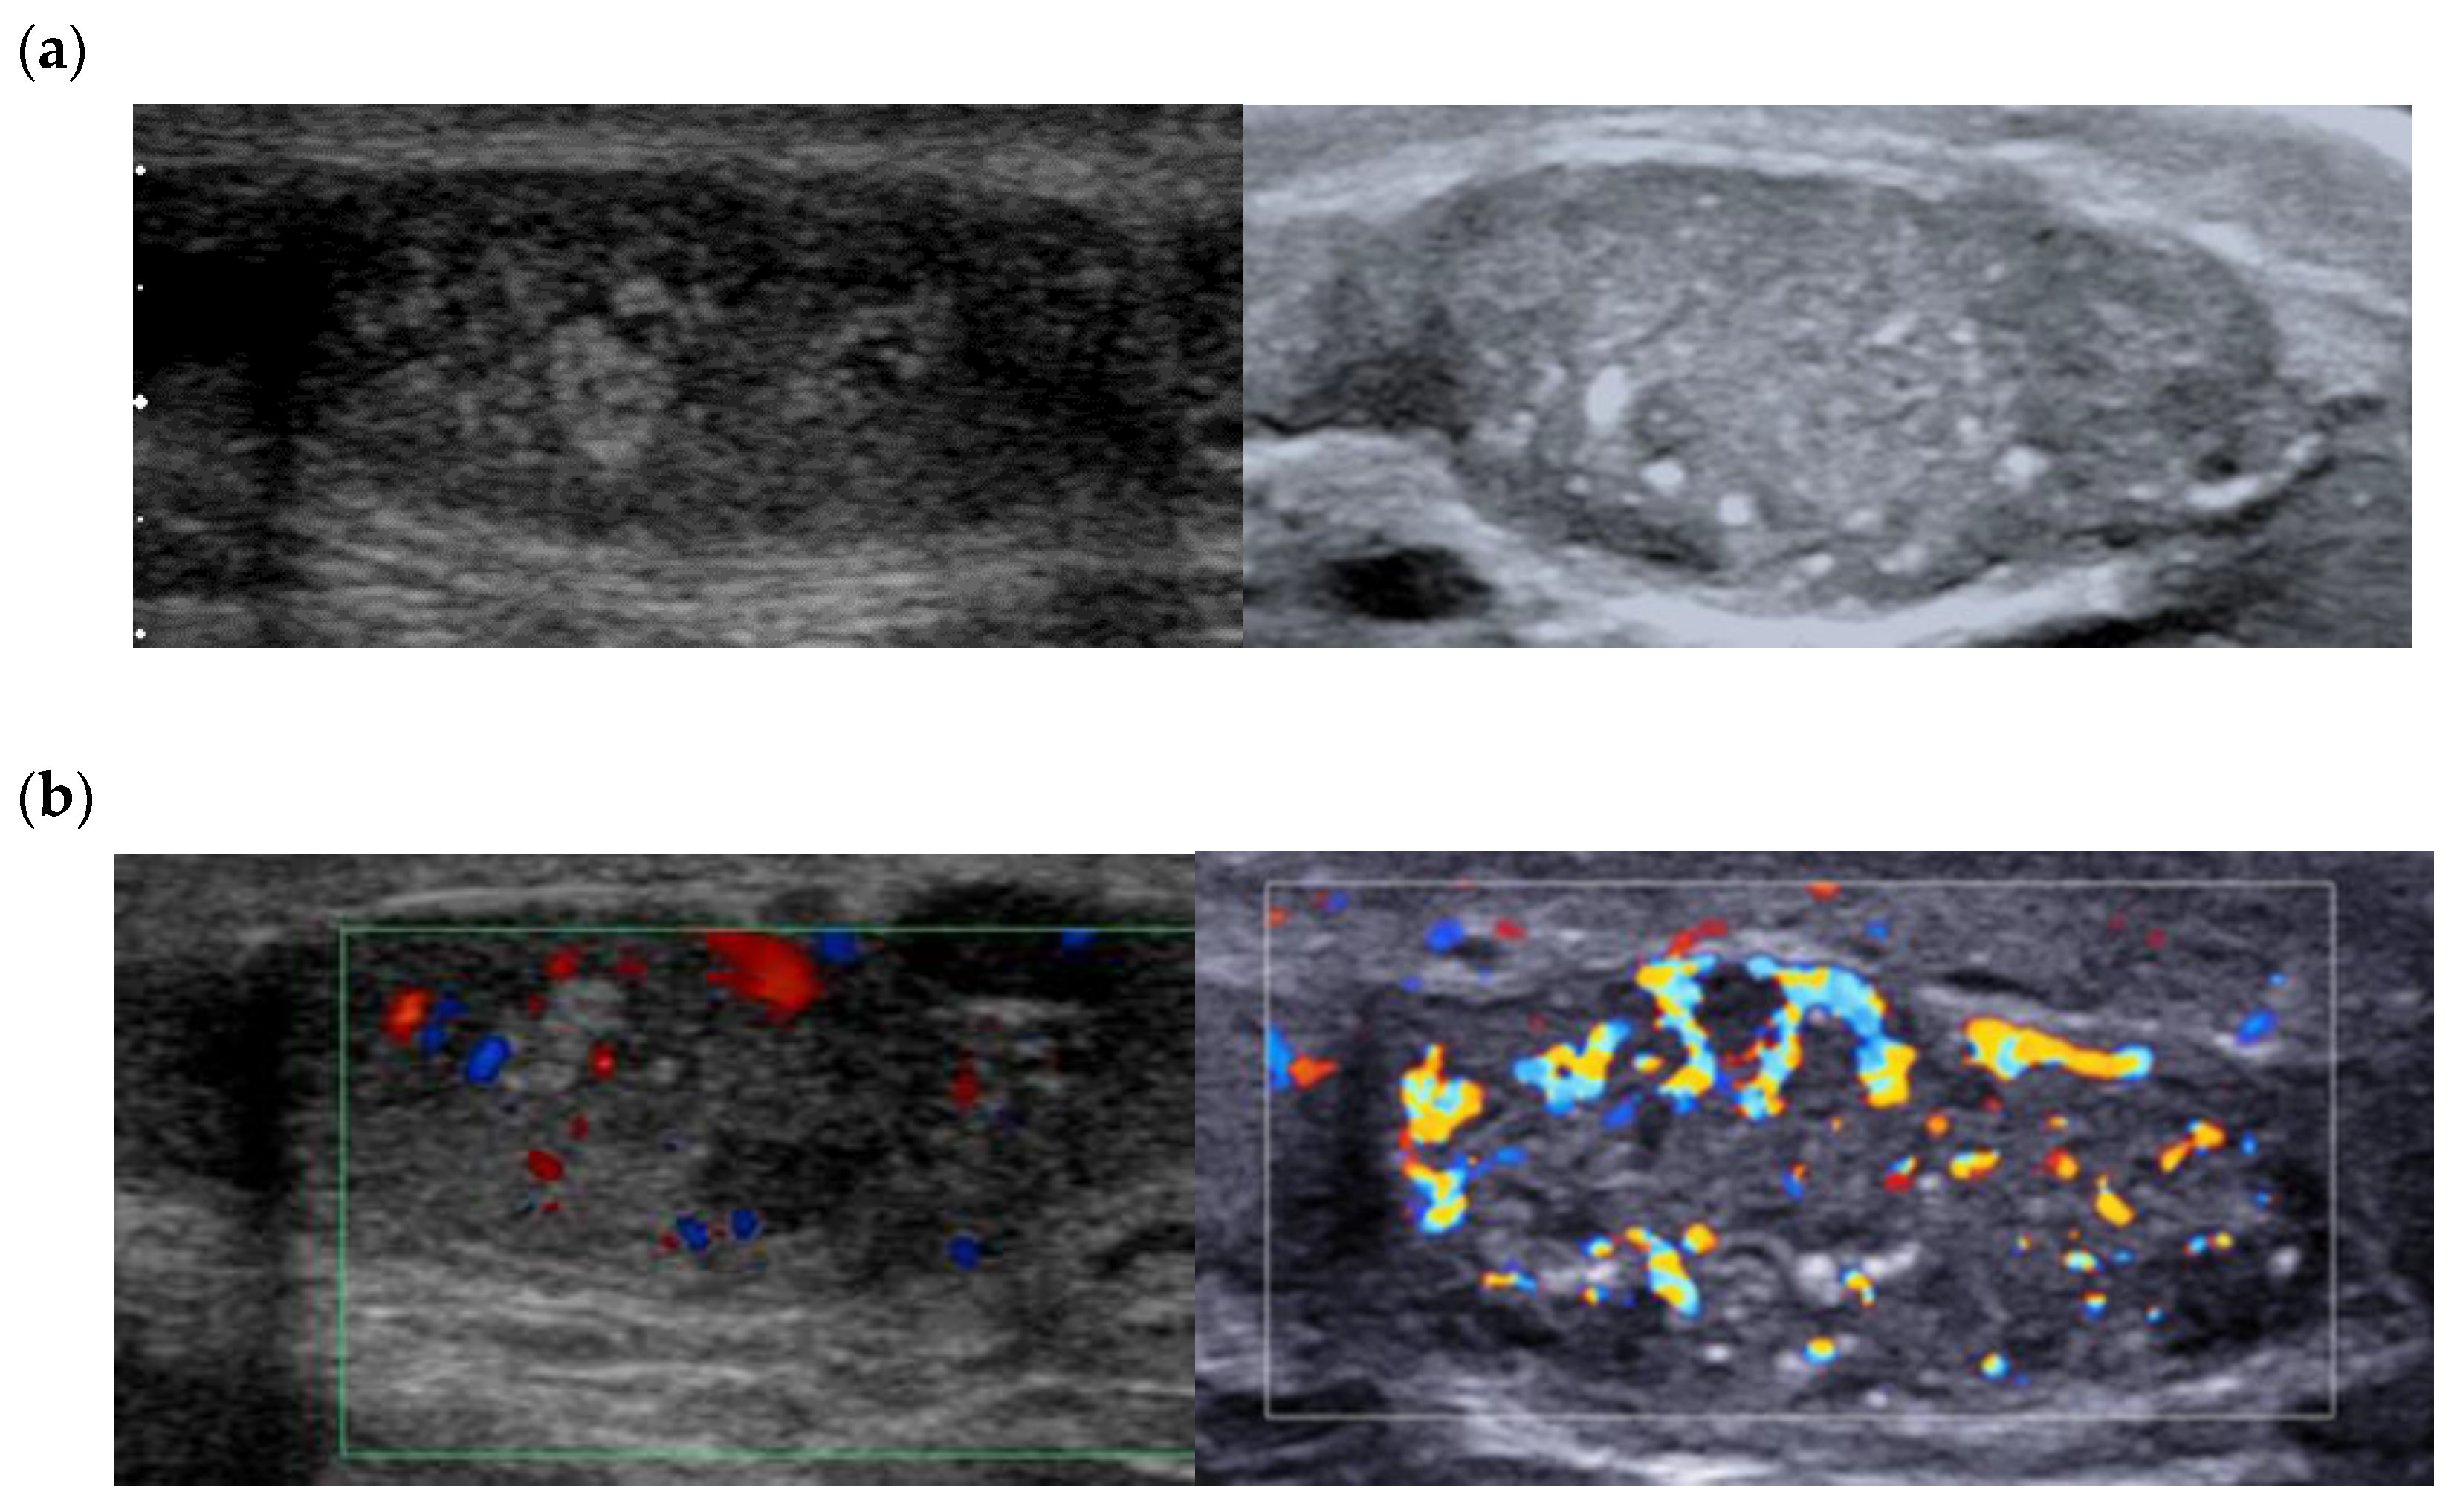

5. Leydig Cell Hyperplasia/Tumor Associated with Klinefelter Syndrome